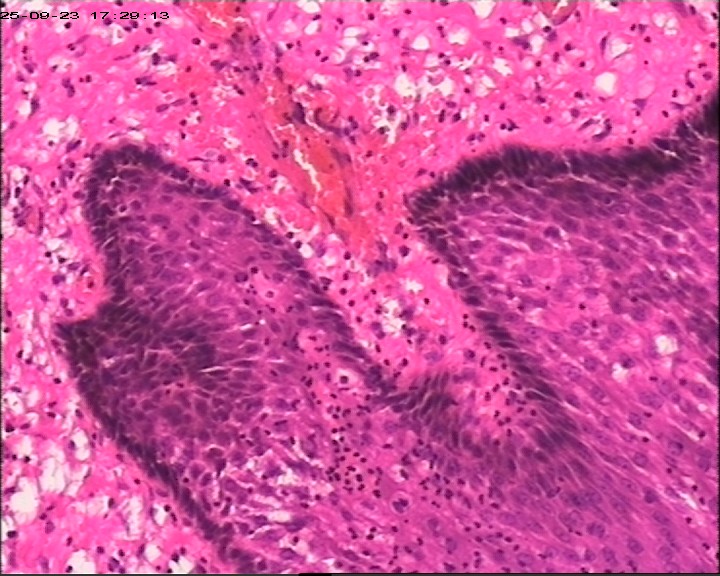

肛周脓肿组织,请帮忙看看,谢谢

肛周出血肿块伴疼痛,红肿6天。脓肿切开引流术+内痔结扎术

臀部皮肤病损

灰白灰红带皮组织3块,大小为3*2*0.5cm

鳞状上皮增生伴湿疣样改变

生炎+出血。

急、慢性炎,伴出血。